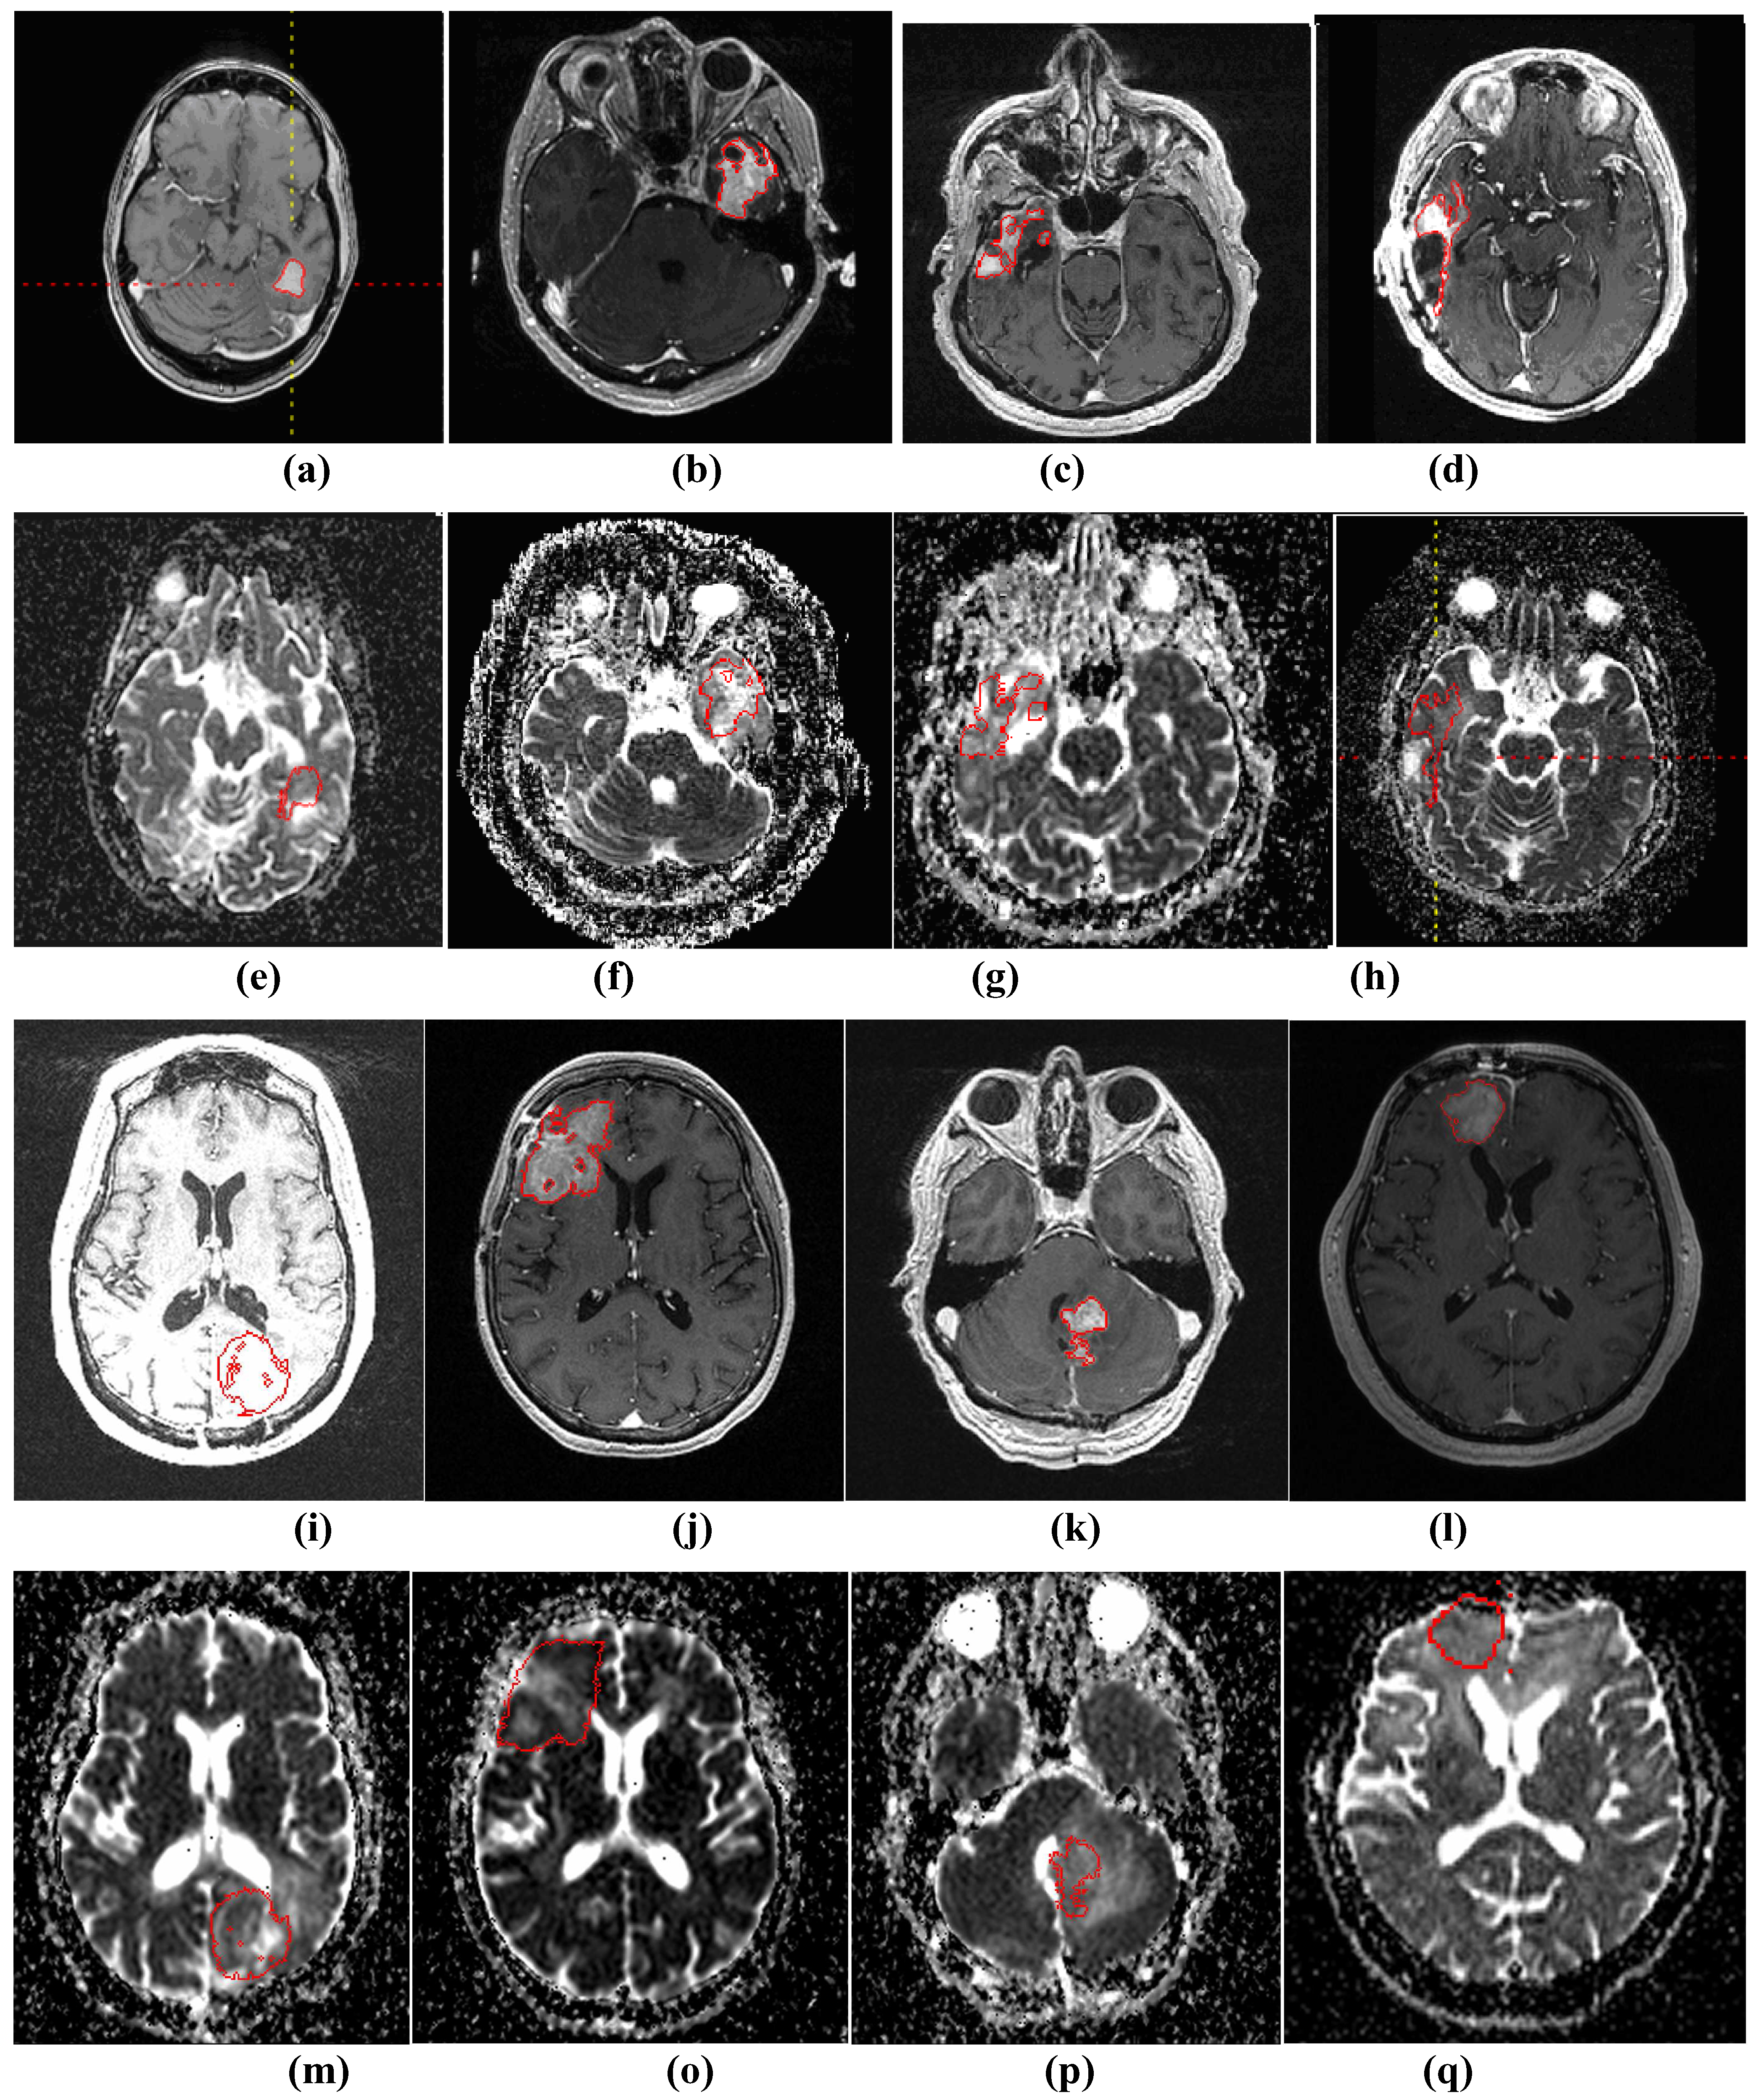

Figure 3 shows four examples of segmentation on T1wCE images and the mapped results on the derived ADC maps.

Figure 3.

(a)-(d) and (i)-(l) show four examples of tumor segmentations on T1wCE images; (e)-(h) and (m)-(p) show the corresponding mapped tumor contours on ADC maps.

For quantitative evaluation of the tumor segmentation mapping results, we randomly selected 31 subjects’ baseline data. The 31 tumors are from an ADC mapping database, 20 of which have different image resolutions between the T1wCE and ADC images in all three dimensions and 11 of which have exactly the same 3D image resolution in both modalities. We calculated the overlap ratio between the mapped ROI generated automatically by the tool and an ROI corrected by a neuro-radiologist. The overlap ratio (OR) is defined by Equation 6, where A and B are two tumor ROIs and size(.) is the number of voxels in that ROI.

The results are shown in Table 3 with 20 out of 31 ROIs (64.5%) have an overlap ratio over 90%.